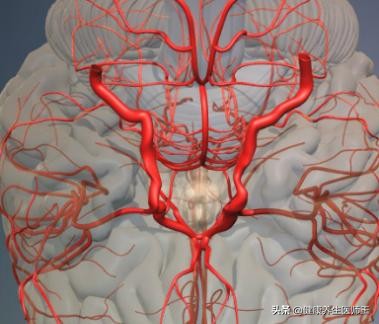

1. 动脉粥样硬化 主要发生在管径500μm以上的动脉,其斑块导致管腔狭窄或血栓形成,可见于颈内动脉和椎一基底动脉系统任何部位,以动脉分叉处多见,如颈总动脉与颈内外动脉分叉处,大脑前、中动脉起始段,椎动脉在锁骨下动脉的起始部,椎动脉进入颅内段,基底动脉起始段及分叉部。脑动脉粥样硬化常伴高血压病,两者互为因果,糖尿病和高脂血症也可加速动脉粥样硬化的进程。

1、 病理 脑梗死发生率在颈内动脉系统约占80%,椎一基底动脉系统约为20%。闭塞好发的血管依次为颈内动脉、大脑中动脉大脑后动脉大脑前动脉及椎一基底动脉等。闭塞血管内可见动脉粥样硬化或血管炎改变、血栓形成或栓子。局部血液供应中断引起的脑梗死多为白色梗死,大面积脑梗死常可继发红色梗死(即出血性梗死)。缺血、缺氧性损害表现为神经细胞坏死和凋亡两种形式。